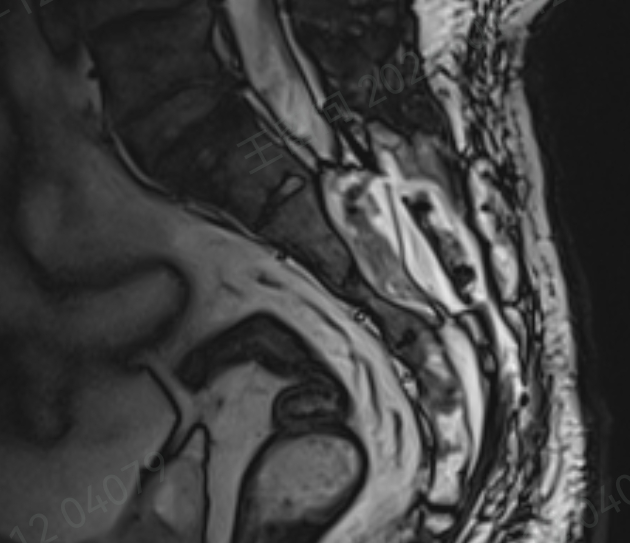

接诊后,孙红山副主任医师团队立即为刘先生展开全面评估,结合详细问诊和复查的核磁共振(MRI)结果,明确诊断其疼痛的根源正是骶管囊肿。

骶管囊肿发生在脊柱尾端的骶管内,由于先天发育缺陷或后天创伤等原因,骶管内部结构变得薄弱,直立状态下,脑脊液会遵循 “水往低处流” 的原则,单向流入神经根袖,长期下来导致神经根袖膨胀,形成充满脑脊液的水囊样肿物。

作为诊断和鉴别骶管囊肿的 “金标准”,MRI 虽能清晰显示病灶,但由于大众对这种疾病普遍缺乏正确认识,临床中误诊漏诊情况时有发生。

而刘先生的疼痛,正是因为囊肿内的神经根被牵拉,同时邻近神经根受到挤压,才导致了持续性的腰骶部疼痛,并非简单的腰肌劳损。

针对刘先生的病情,团队经过详细评估,制定了个性化手术方案。手术中,孙红山在显微镜和神经电生理监测下,精准找到囊肿内微小的脑脊液漏口,取刘先生自身的脂肪组织填塞漏口,随后分离囊壁并缩窄缝合,重建神经根袖,外部再用人工硬膜加固。